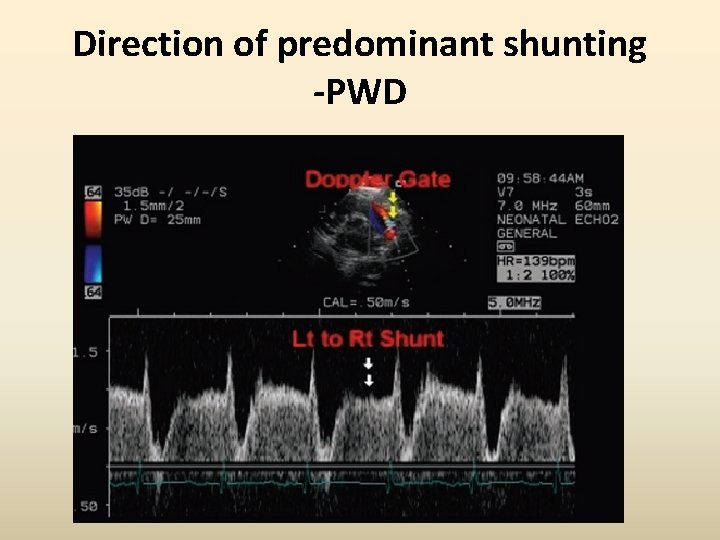

Direction of predominant shunting -PWD